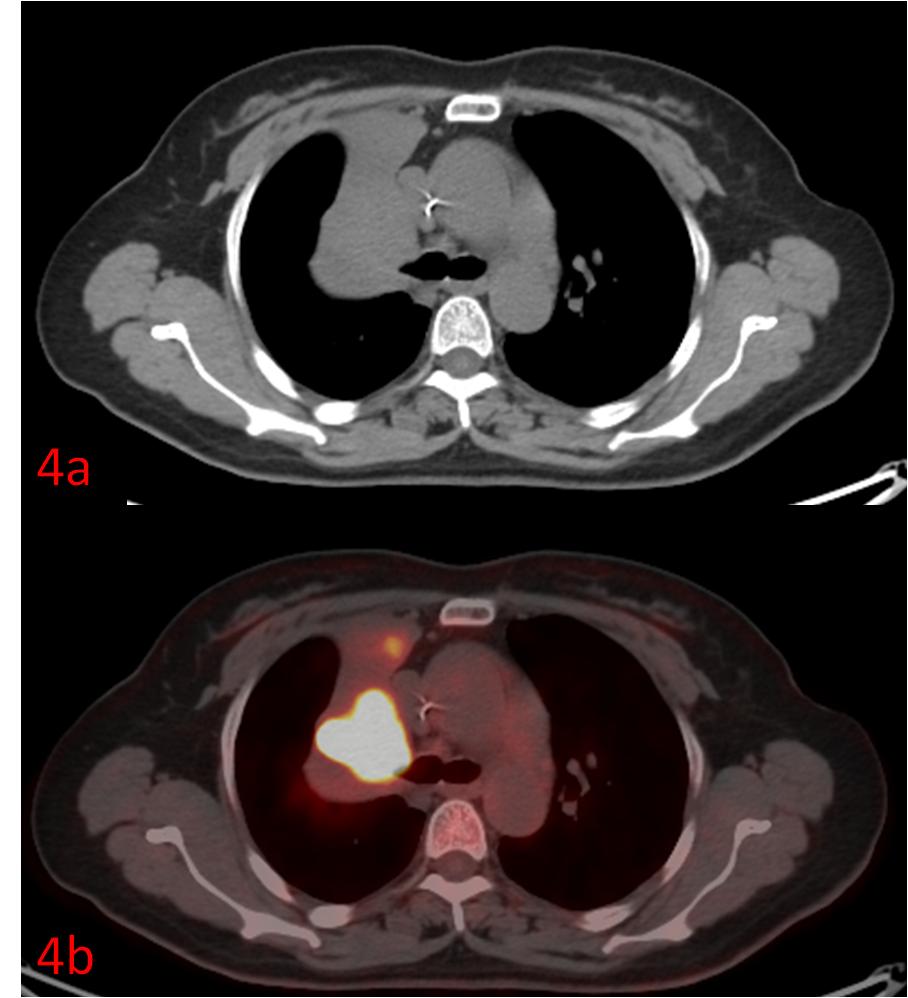

例4:中年女性,右肺上葉小細(xì)胞癌伴右肺上葉不張、阻塞性炎癥,常規(guī)CT無法區(qū)分腫瘤和不張的肺組織(圖4a),PET/CT清晰展示了腫瘤的邊界(圖4b)。